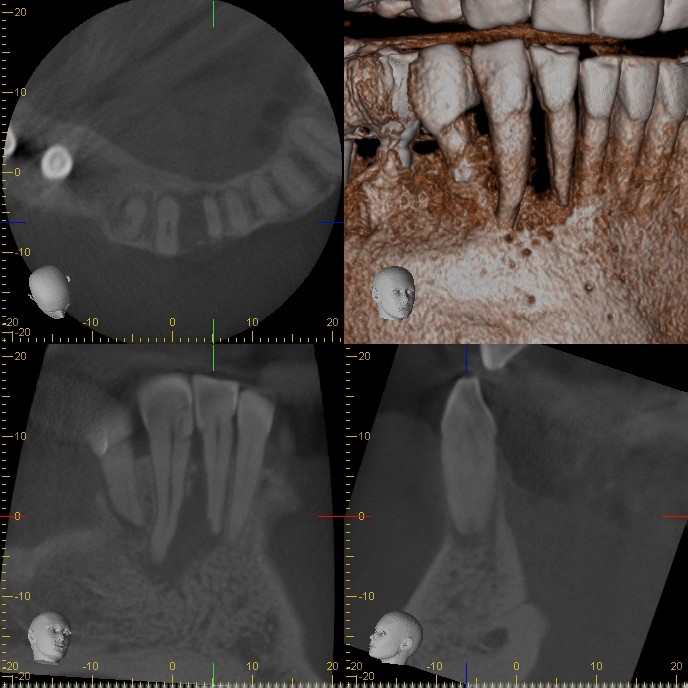

| CBCT shows the apical and lateral bone loss on #26 and #27. The lateral bone loss on #27 is also suggestive of a possible root fracture, but since the tooth is necrotic, radiographic appearance alone is not enough evidence to diagnose this with a root fracture. CBCT also shows a 2 canaled root form on #26. |

| There was concern of a possible root fracture, but none could be see internally with microscope. CaOH medicated dressing was placed after initial debridement and NaOCl irrigation. |

| After 3 months in CaOH, we opened and examined again and could find no fractures. Another application of CaOH medicated dressing was placed. |

| After 6 months of CaOH therapy we saw significant bone healing. The canals were obturated and case completed. |